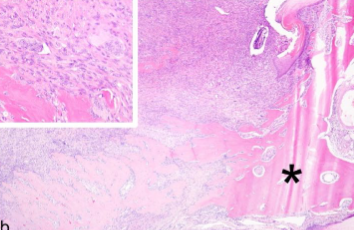

고양이 지골에서 발생한 골 거대 세포 복구 육아종 증례

드물게 발생하는 골 거대 세포 복구 육아종 증례에 대한 보고가 나왔다.

드문 질환에 해당하기에 유사 병변에서 이 질환으로 몰입될 필요는 없지만 알아야 보이는 것이고, 언제나 그렇듯 백문이 불여일 조직검사이니, 조직검사를 반드시 하자.